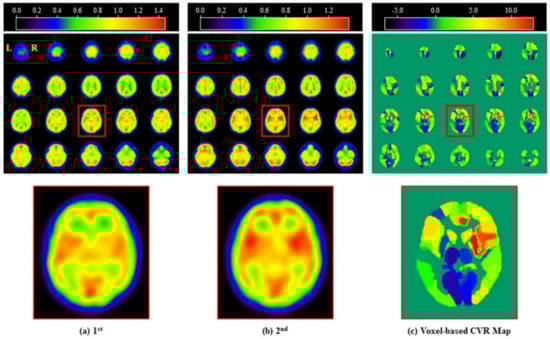

Figure 3. Standardized display supporting the assessment of the SPECT images obtained, including (a) first, (b) second, and (c) voxel-based CVR Map of a representative subject. The colored bars indicate the signal intensity in both (a) and (b), and the CVR (%) value in (c), respectively. Abbreviations: L, left; R, right.

The pre-processed first and second SPECT images of a representative subject are shown in Figure 3. In the second image, there was an increase in signal intensity in the frontal, temporal, and occipital cortices and the cerebellum compared to the first image. However, there were no specific values demonstrating increases in target ROIs between the first and second images. As shown in Figure 3c, there was a quantitative difference between the two SPECT images in a total of 116 ROIs on the voxel-based CVR map. The mean CVR value in the cerebellum was −2.28%, which was used for the relative CVR values in subgroup ROIs.